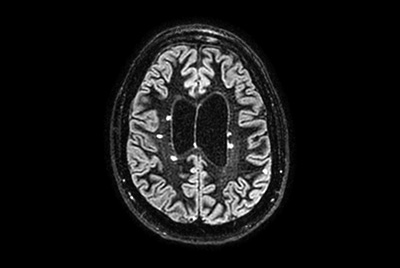

Brain - White matter lesions

Multiple Sclerosis versus TIA

Brain Multiple Sclerosis

FLAIR* protocol for Multiple Sclerosis